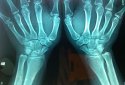

超声骨密度仪测试后,骨密度是否有差异? 有方法可以增强孩子骨密度吗?骨密度测试是通过外部仪器或工具来测量骨骼的密度并了解骨骼的状况。 这种测试特别适合老年人和儿童。

据了解,骨密度测量主要分为超声骨密度检测仪和x射线骨密度仪。这是医院经常购买的两种骨密度设备。大多数骨密度测量是准确的。你希望它们100%准确。我敢说没有制造商能保证这一